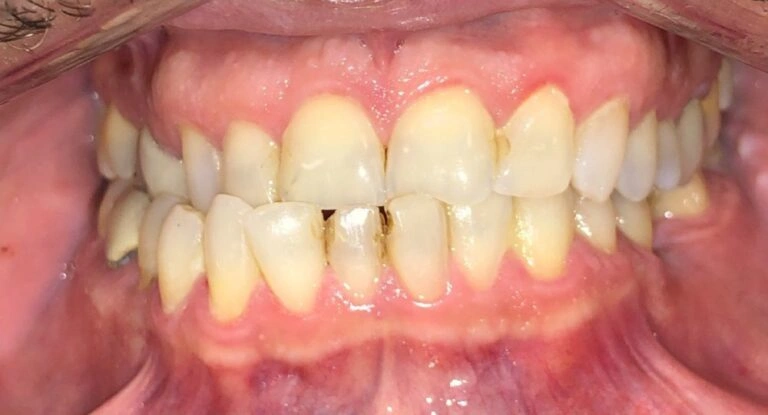

Why should you worry? If a deep bite goes unaddressed, the teeth don’t meet properly. This misalignment can cause severe wear and tear on the teeth over time, eventually leading to tooth breakage and even tooth loss. I’ve treated many adults who came in with worn-down teeth due to untreated deep bites.

Here’s a visual example of what this looks like:

Patient Example #1: Notice how the teeth are significantly worn down and chipped due to long-term misalignment.

Patient Example #2: A more severe case where untreated deep bites led to significant tooth wear and difficulty chewing.